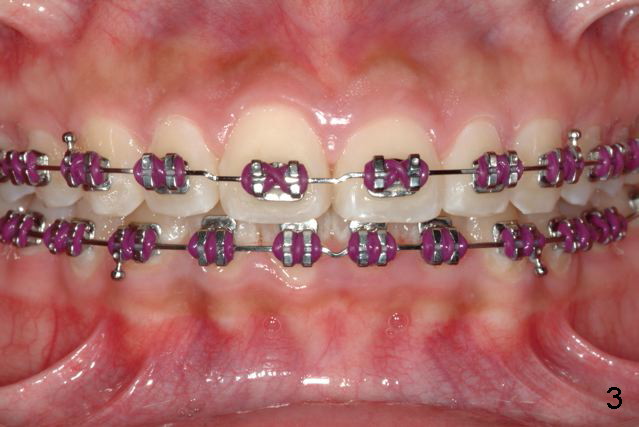

Excellent thinking.  According to the final photos, you must have done something to overcorrect the rotation of the two centrals.  Did you do it with purpose or by accident?  How did you do it, although Amy may not like it.  It seems to me that there is no practical way to overcorrect rotation.